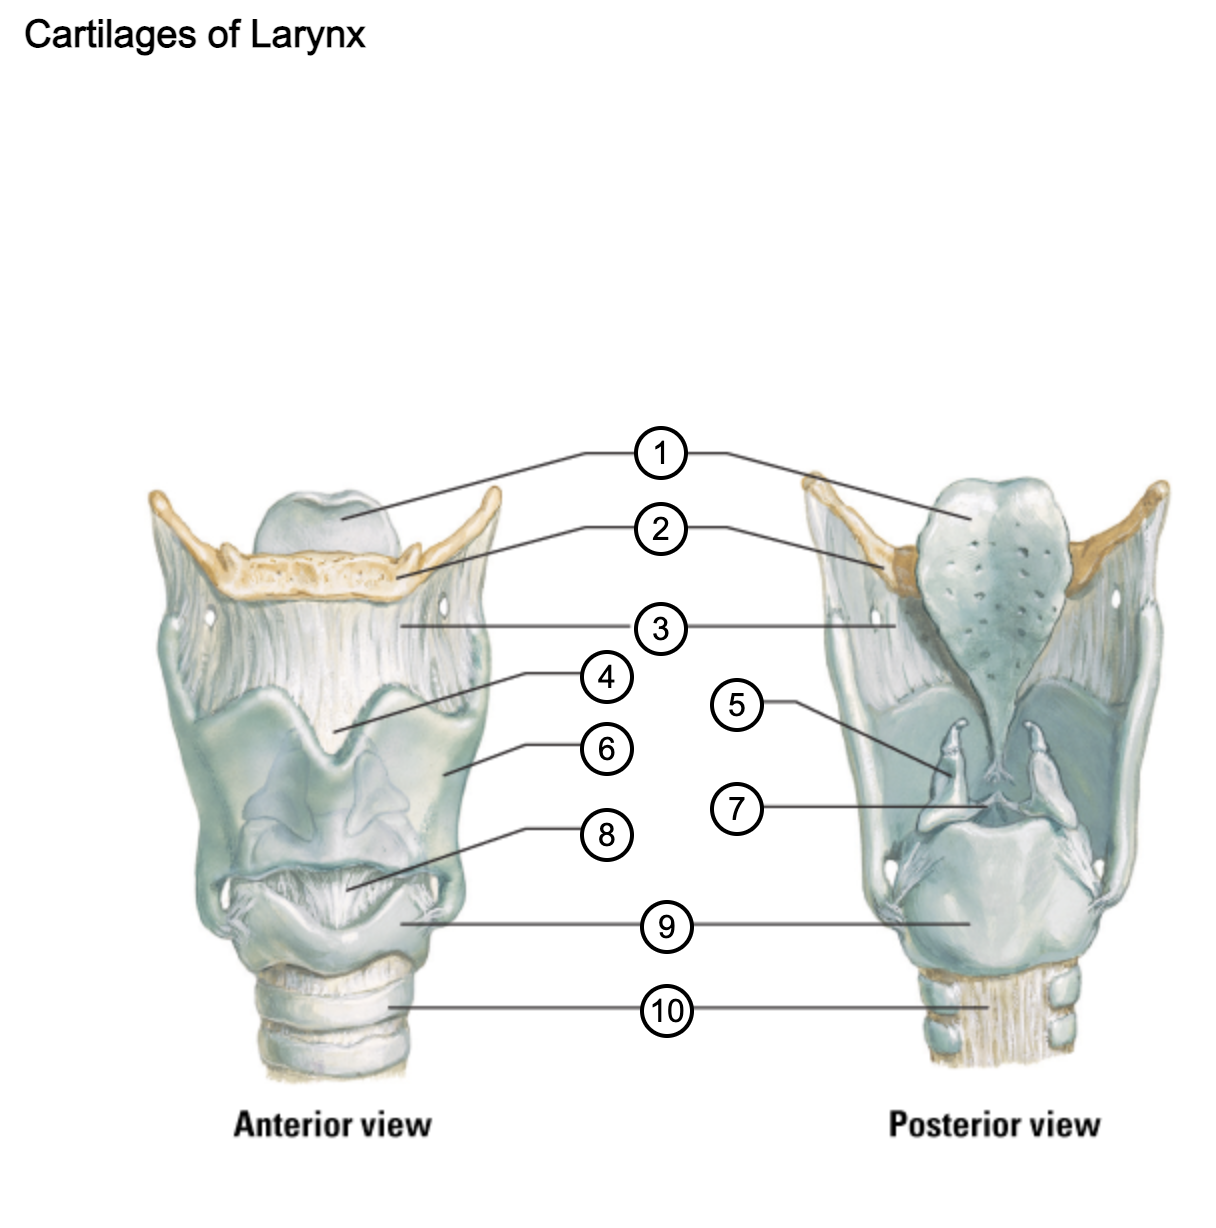

1

epiglottis

2

hyoid bone

3

thyrohyoid membrane

4

superior thyroid notch

5

arytenoid cartilage

6

lamina of thyroid cartilage

7

vocal ligament

8

median cricothyroid ligament

9

cricoid cartilage

10

trachea